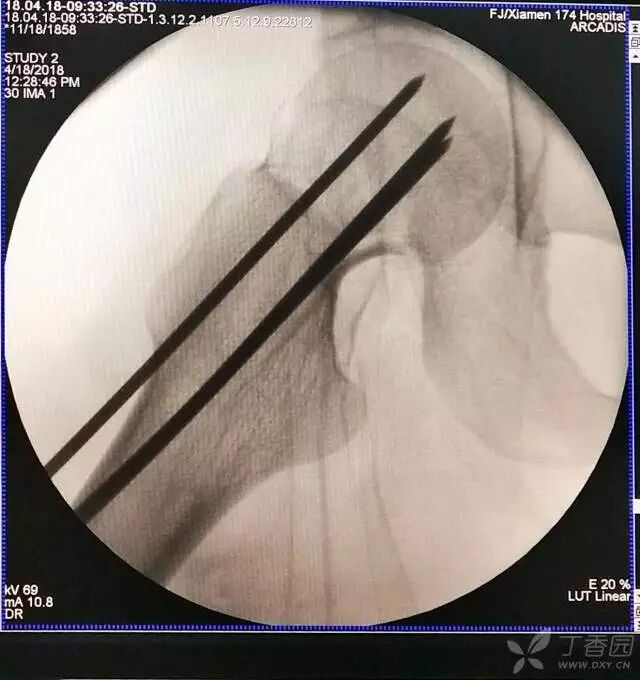

5. 打入第一枚倒品字下方导针,跟体外导针基本重叠

牵引床怎么用视频详解:如何不使用牵引床做好一台股骨颈骨折?_https://www.jmylbn.com_新闻资讯_第13张

6. 然后依次打入倒品字上方的两枚导针